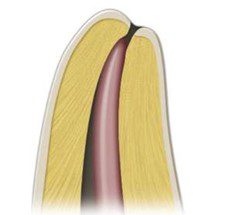

Trong kỹ thuật lèn ngang nguội cổ điển, côn chính là côn 0.02 với kích thước đầu tương ứng với kích thước trâm chóp chính (MAF) mà ống tủy đã được sửa soạn. Côn được chọn nên đặt vừa đến chiều dài làm việc, không thể đẩy quá chiều dài làm việc và có cảm giác kháng lực nhẹ khi rút ra khỏi ống tủy. Lực kháng này (gọi là tug-back) cho thấy côn đang kẹt vào thành ống tủy (hình 14.11).